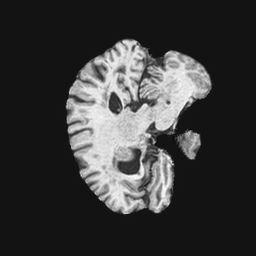

Exp. 1: Segmented adult brain data is used to evaluate our network’s regression performance with known ground truth . 85 brains from the ADNI data set[1] were randomly selected; 70 brains for and 15 brains for . Fig. 2 shows an example slice of the ground truth and the reconstructed .

Each brain has been centered and re-sampled in a volume. Using the Fibonacci Sphere Sampling method, a density of 500 unique normals is chosen with 64 sampling planes spaced evenly apart on the Z-axis (giving a spacing of 4mm). This therefore yields a maximum of 32000 images per brain; 2.24M for the entire training set and 345K for the entire validation set. After pruning with little or no content, this figure drops to approximately 1.2M images for training and 254K for validation. Training took approximately 27hrs for 30 epochs.

Reconstructing from initialisation without SVR yields a PSNR of 23.7 1.09; with subsequent SVR the PSNR increases to 29.52.43 when tested on 15 randomly selected test volumes after four iterations of SVR.

0..5 Randomly selected illustrative inference results

Here we show for Exp. 1, Exp. 2, and Exp. 3 randomly selected examples of images that have been presented to the network (ground truth) compared to an image sampled at the predicted location.

In these experiments, we present a ground truth (GT) image to the network to estimate the respective transformation parameters needed to reorient the slice in its correct world co-ordinates. Using the transformation parameters, we generated a slice from the 3D atlas in the location where the network has predicted that slice should be (denoted as SVRNet).

The slices are compared side-by-side to give a visual representation of “where the slice really is” and “where the network thinks the slice is”.

0..5.1 Exp. 1:

Slices, extracted from a correctly registered and reconstructed 3D volume, from the testing data set are presented to the network. The predicted slice is extracted from the same volume, using parameters estimated by SVRNet as shown in Fig. 8 and 9.